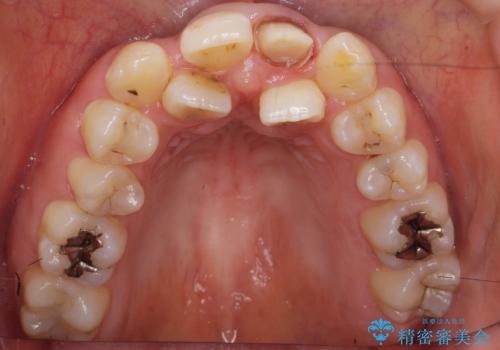

- 前歯が黒くなってきたことを主訴に来院された患者様です。

精査したところ、う蝕により歯の内側から黒くなっていました。

根管治療後、セラミッククラウンによる補綴を行いました。

※う蝕が大きく健全歯質が非常に薄いため、長期的予後に関しては不明であることをご理解頂いた上で治療を行いました。